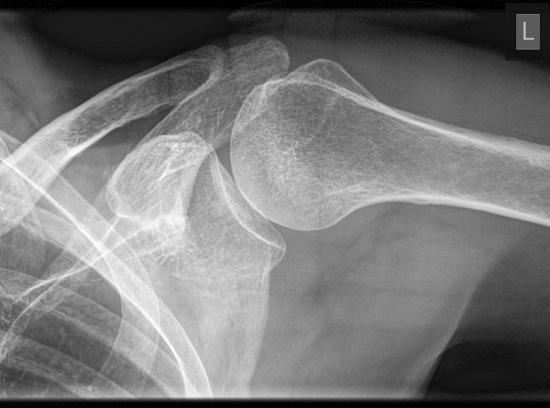

肩关节有哪些稳定结构?

肩关节由肩胛骨的盂肱窝及肱骨头构成,又称盂肱关节,是人体活动范围最大、最具灵活性的关节。肩关节是一个典型的球窝关节,其构造犹如一个